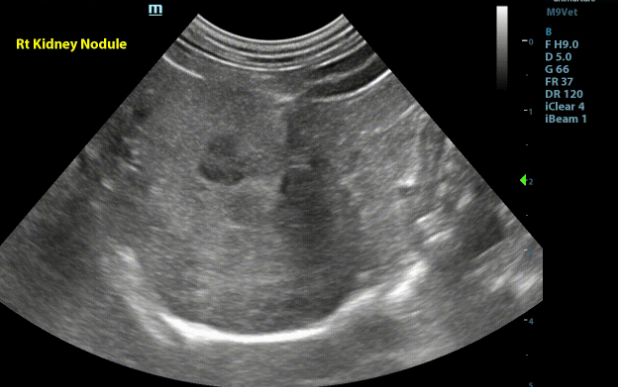

Kidneys - Both kidneys were found to have normal size (Lt/Rt = 3.8 /4.0cm). With a normal overall shape with coarse mild to moderately hyperechoic renal cortices which are mildly enlarged. There was mild loss of the corticomedullary junction distinction. There were a few small thin-walled anechoic cortical cysts seen throughout both kidneys. There is a homogenous, well defined, hypoechoic very mildly capsule deforming nodule affecting the corticomedullary region in the convex portion of the right kidney. (1.1x0.8cm)

Image 2: Right kidney in transverse with hypoechoic nodule